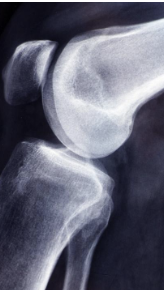

무릎 십자인대 파열 증상 및 십자인대 파열에 대해 알아보는 시간 갖도록 하겠습니다.

십자인대는 무릎 관절 내부에 있는 4개의 인대 중 하나로, 대퇴골과 승골 사이에 위치해 있습니다. 십자인대는 무릎 관절의 안정성을 유지하는 역할을 담당합니다. 무릎 관절에 직접적인 충격이 가해지거나, 무릎이 강한 스트레스를 받았을 때 십자인대가 손상되는 경우가 있습니다. 이러한 십자인대 손상은 스포츠 활동이나 사고 등으로 발생할 수 있습니다. 십자인대 손상 증상으로는 무릎 통증, 부종, 불안정감 등이 있으며, 심한 손상의 경우 수술이 필요할 수도 있습니다. 십자인대 손상을 예방하기 위해서는 적절한 스포츠화를 착용하고, 몸을 충분히 기르며, 스포츠를 할 때 안전장비를 착용하는 것이 중요합니다.